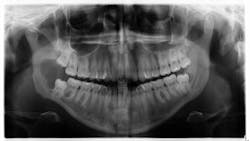

Patient: 22-year-old female

- Patient referred to oral surgeon for removal of wisdom teeth

- Following that, all contact with patient was lost

Seven years later …

- Large radiolucent lesion

- Significant bone destruction in mandible

- Inflamed tissue

- Tender to palpation

Dangerous lesion if left untreated